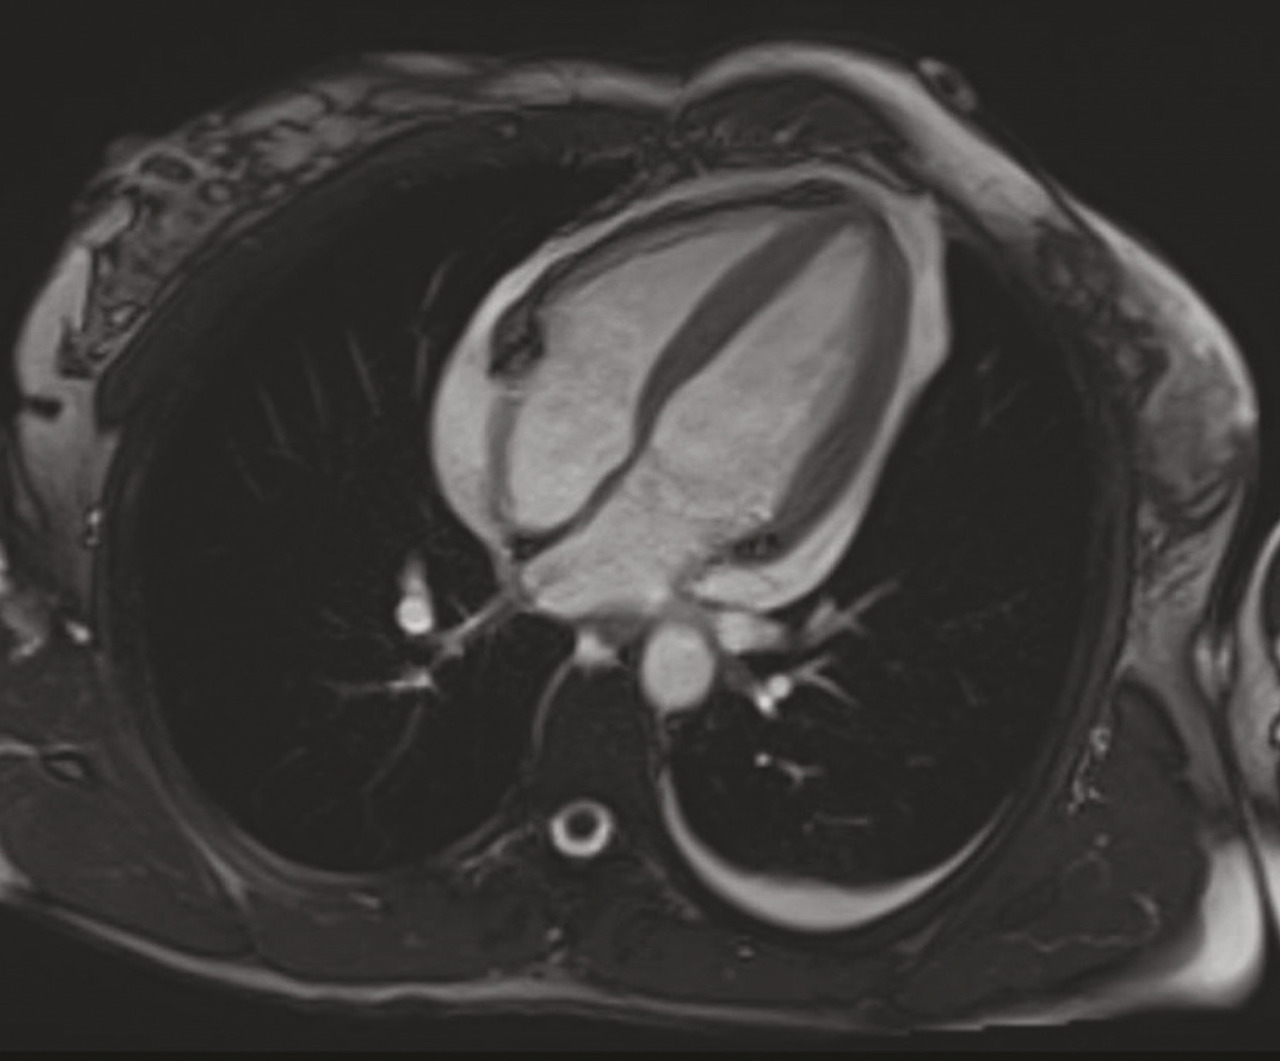

L’imagerie par résonance magnétique (IRM) cardiaque (fig. 2) confirme l’inflammation du péricarde, ce dernier étant épaissi et brillant en T2 et rehaussé après injection de gadolinium, et permet de rechercher une myocardite associée. Les biopsies péricardiques sont réservées aux tamponnades récidivantes, aux suspicions de péricardite bactérienne ou néoplasique, et aux cas de péricardites s’aggravant sous traitement sans cause définie.

Le diagnostic est conforté par la tomodensitométrie et l’IRM cardiaque, qui permettent la mesure de l’épaisseur du péricarde (> 4 à 6 mm), la recherche de calcifications et de signaux inflammatoires. L’échocardiographie montre une fonction systolique conservée, des anomalies de la fonction diastolique et des anomalies de la cinétique du septum interventriculaire. Le Doppler du flux transmitral montre un profil restrictif. Un cathétérisme cardiaque est parfois nécessaire pour confirmer le diagnostic, notamment en cas de difficultés échographiques.